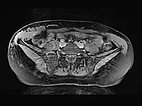

Die transversale, T2-gewichtete, fettunterdrückte MRT auf Höhe der Beckenschaufel zeigt die Ausdehnung der LM auch im Bereich der rechten Flanke. Nur die epifaszialen Anteile der Bauch- und Rumpfwand sind betroffen.

Die transversale, T1-gewichtete, fettunterdrückte MRT nach Kontrastmittelgabe zeigt nur ein minimales Enhancement der dünnen Wände der lymphatischen Malformation. Dies ist typisch für eine LM.